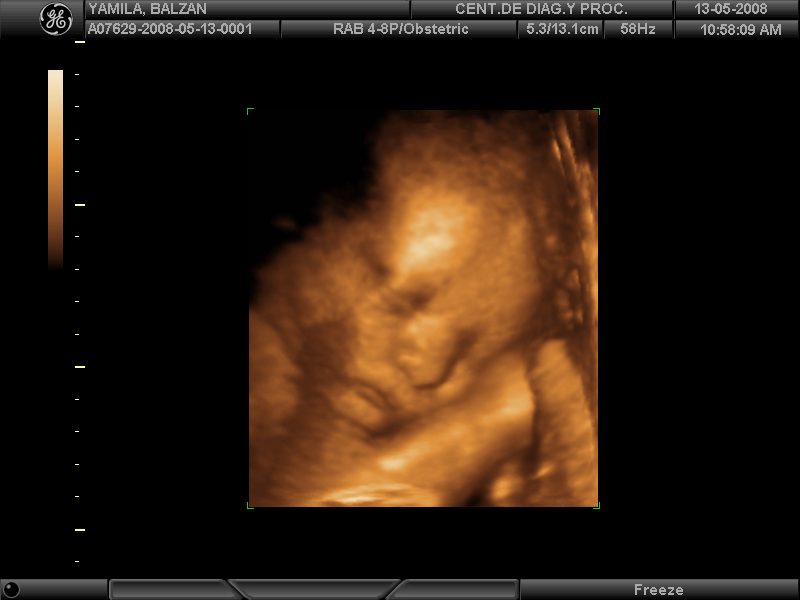

Subject: RV: Yamila Balzàn-Clinica de Imagenes0001.pdf Mami les mando el resultado del estudio

que me hicieran hoy por la mañana. Según me dijo el doctor estaba inflamadito el

riñón derecho pero tampoco nada alarmante. Tambien les mando una preciosa foto del

guapisimo del año: Carlos Andrés Palacios Balzán. Verdad que se parece a Yamilita y a

Nathalia?.Tal vez es temprano decirlo como me dice mi querido esposo, pero yo lo

veo igual. Besos y